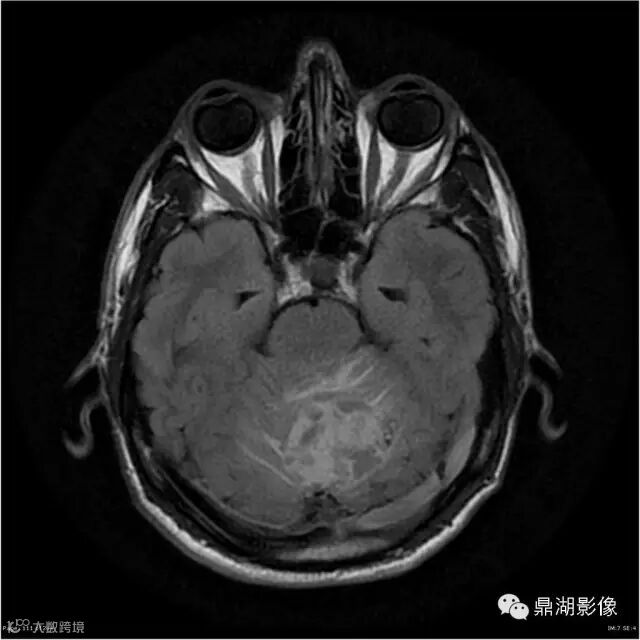

Axial T1WI

T1WI

影像:可见一个约43 x 36 x 31mm的从小脑蚓部延伸而来的占位,T1WI、T2WI呈高低混杂信号,病灶周边见流空血管影及水肿带,增强病灶明显强化,中心见无明显坏死区,它紧靠左小脑幕上。第四脑室受压变窄,室管膜水肿,可见脑桥及延脑扁桃体进入枕骨大孔。

本例为一例实质性血管母细胞瘤。实性血管母细胞瘤CT平扫示病灶呈等或高密度,增强后可见明显强化。MRI平扫通常病灶很不均质,T1呈稍低信号为主的较混杂信号,T2呈等、高信号,DWI通常呈低信号或等信号。文献报道,实性血管母细胞瘤较典型的表现为瘤内及瘤周扩张的流空血管影,瘤周中、重度水肿。因此,小脑半球区的单发肿块伴流空血管影,周围大片水肿以及增强后肿块明显强化"形态规则"边界清楚,此时应将实性血管母细胞瘤考虑在内。